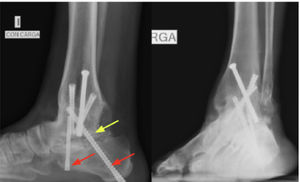

En este contexto se decide realizar una nueva revisión. Para esto se realiza artrodesis de revisión tibiocalcánea donde se aumenta estabilidad y rigidez del constructo con placa posterior tibiocalcánea con tornillo de compresión interfragmentaria a través de la placa+tornillo retrógrado calcáneo talar. Se realiza resección de pseudoartrosis, tejido óseo no vital y preparación de remanente de superficie articular subtalar posterior+agregación de autoinjerto de tibia proximal y aloinjerto de cresta ilíaca y augmentación con plasma rico en plaquetas (PRP) en julio de 2024 (figura 2). La línea de tiempo del caso clínico se detalla en la figura 3.

Proyecciones anteroposterior, mortaja y lateral de tobillo izquierdo. Resultados post op cirugía de revisión. Se aprecia aumento de la rigidez de constructo mediante una placa posterior tibiocalcánea (flecha azul), tornillo compresión interfragmentario a través de la placa (flecha amarilla)+tornillo calcáneo talar retrógrado (flecha roja).